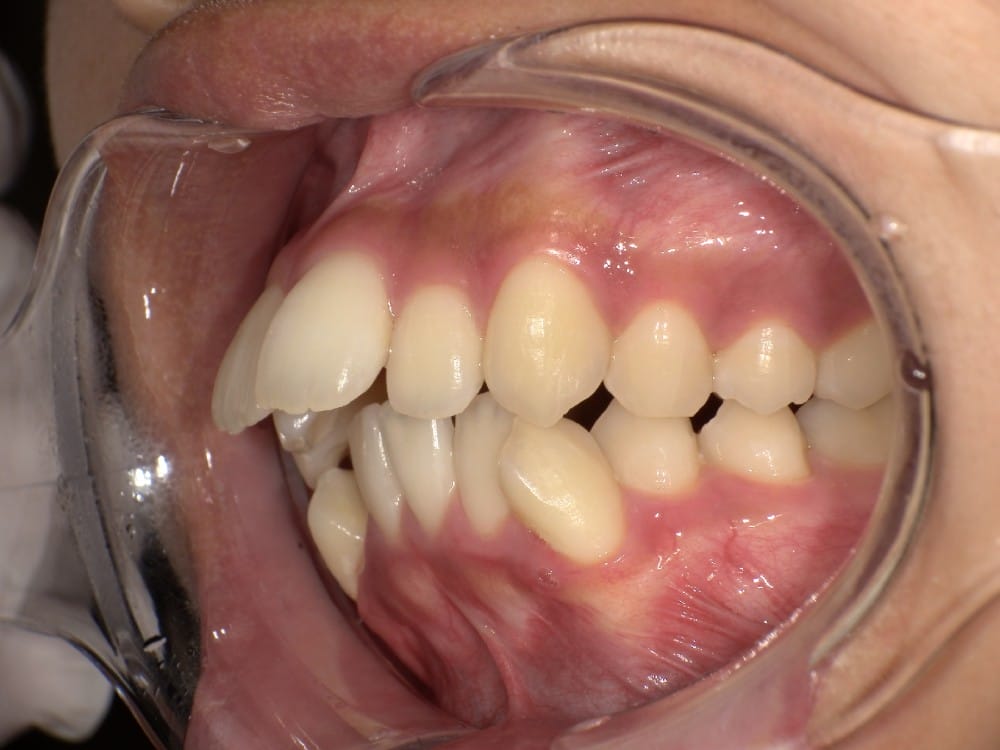

② セファロ(横顔レントゲン)分析

骨格的な問題があるかどうかを数値で評価します。

上顎・下顎の前後関係、前歯の傾斜角度、口元の軟組織のバランスなどを客観的に確認することで、「歯が原因なのか」「骨格が原因なのか」を明確にします。